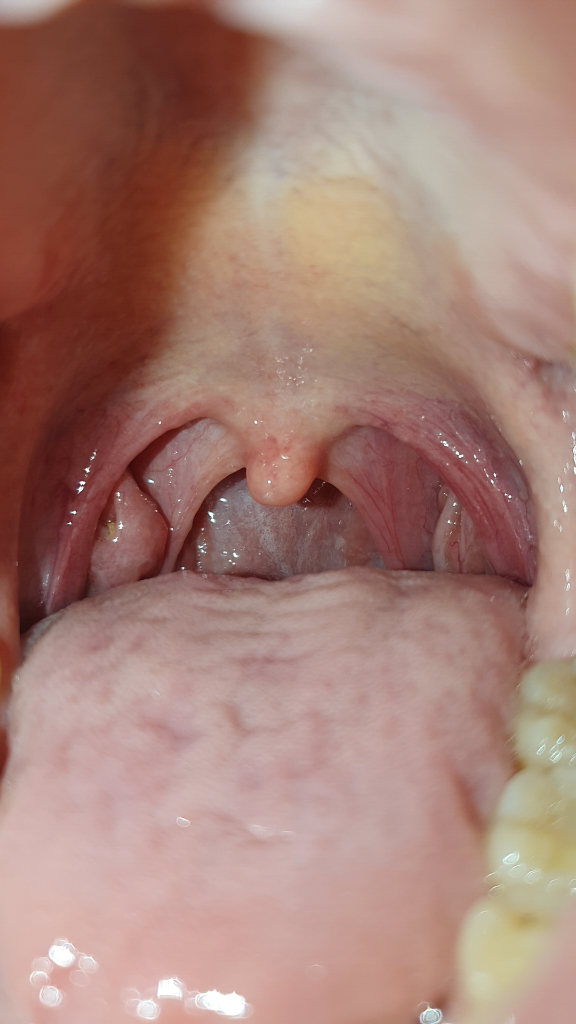

왼쪽에 보면 염증? 같은게 생긴걸 보실수 있는데 무슨 문제가 생긴건지 궁금합니다 인터넷으로 찾아보니까 편도선염이나 역류성 식도염 증상이랑 비슷한데 침을 삼킬 때 이물감을 느끼거나 아무것도 안해도 생선 가시같은 날카로운 무언가가 기도에 낀거같은 이물감이 느껴질 정도로 매우 거슬립니다. 혹시 병원을 갈 정도로 심각한건지 알고싶습니다. 만약에 심각하면 병원에서 어떤 진료를 받아야하는지도 알고싶습니다.

• 2번 째 사진

특별하게 이상은 없어보이며

편도는 다른사람에 비해 큰편입니다. 편도가 크다고 이물감이 발생하지는 않습니다.

아마 주변으로 발적이 있는것으로보아 약간의 염증이 있어 보입니다.

소염제 복용해보세요

• 사진의 소견만으로 정확하게 구분하기는 어렵지만 사진의 소견을 통해서 보았을 때에는 염증이 생겼다기 보다는 편도결석이 있으신 것 같습니다. 관련하여서는 이비인후과적으로 진료 및 검사를 통해서 좀 더 정확하게 감별해 보시고, 편도결석이 맞다면 제거 시술을 받으시는 것을 권고드립니다.